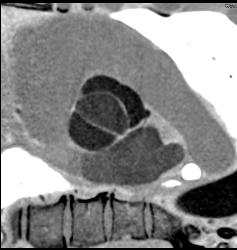

Left Anterior Descending Coronary Artery (LAD) and Circumflex Artery (CX) Arise Directly Off of the Left Cusp